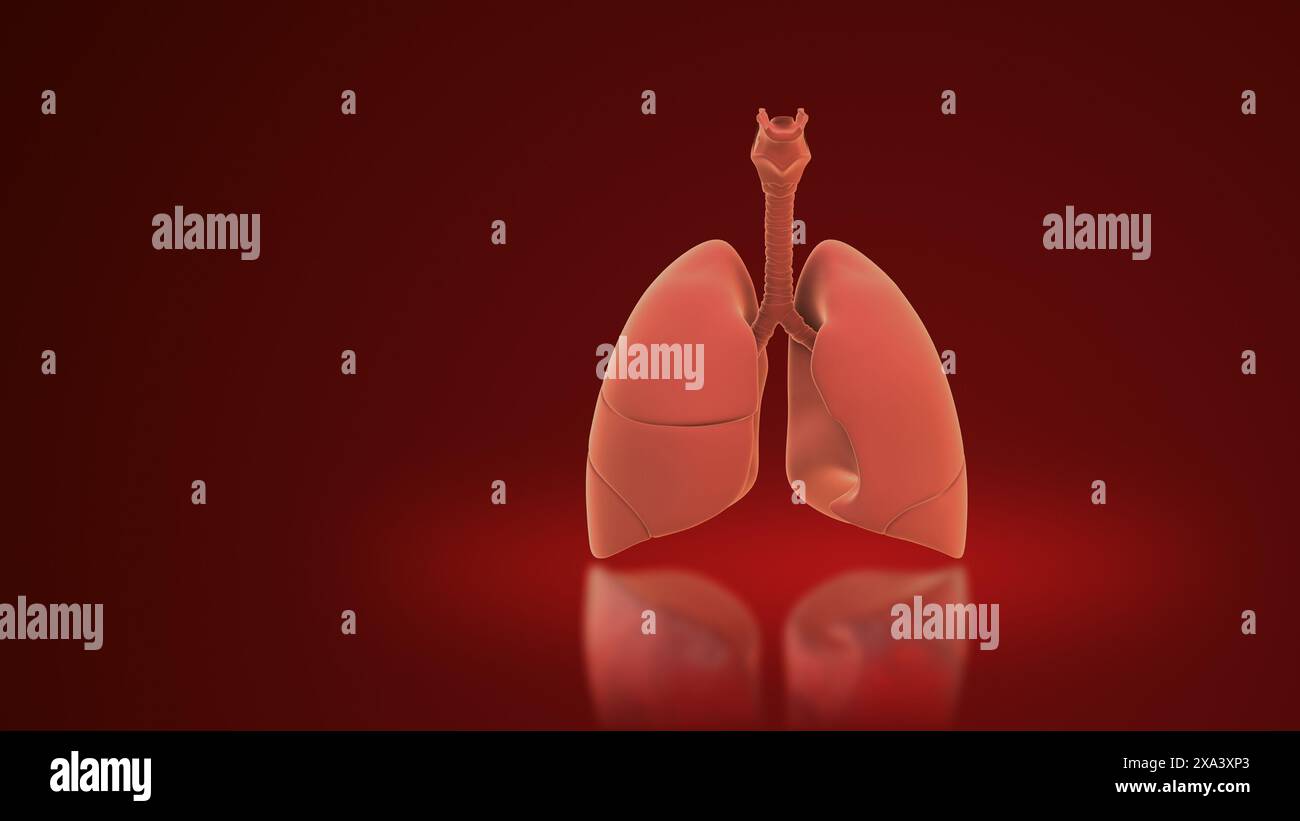

3d Lungs of the Human Respiratory System Stock Photohttps://www.alamy.com/image-license-details/?v=1https://www.alamy.com/3d-lungs-of-the-human-respiratory-system-image608596299.html

3d Lungs of the Human Respiratory System Stock Photohttps://www.alamy.com/image-license-details/?v=1https://www.alamy.com/3d-lungs-of-the-human-respiratory-system-image608596299.htmlRF2XA3XP3–3d Lungs of the Human Respiratory System

The respiratory system and the lungs Stock Photohttps://www.alamy.com/image-license-details/?v=1https://www.alamy.com/the-respiratory-system-and-the-lungs-image608596521.html

The respiratory system and the lungs Stock Photohttps://www.alamy.com/image-license-details/?v=1https://www.alamy.com/the-respiratory-system-and-the-lungs-image608596521.htmlRF2XA3Y21–The respiratory system and the lungs